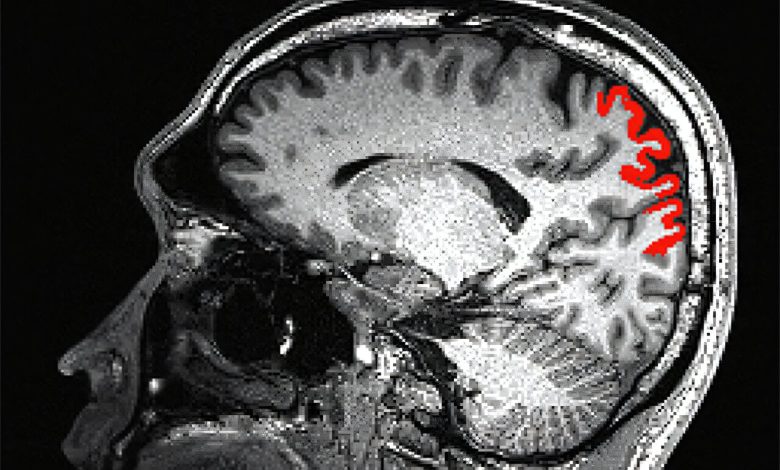

A seção vermelha desta ressonância magnética de um participante do estudo mostra a região parietal superior direita do cérebro. Os pesquisadores descobriram que o maior volume parietal superior direito está ligado a uma melhor função cognitiva, incluindo raciocínio indutivo, memória de longo prazo, memória de trabalho e fluência verbal. Crédito: UT Southwestern Medical Center

Notavelmente, a região parietal superior correta do cérebro desempenha um papel importante na função cognitiva fluida, e os pesquisadores descobriram que o maior volume parietal superior direito estava ligado a uma melhor função cognitiva, como raciocínio indutivo, memória de longo prazo, memória de trabalho e fluência verbal.

Os pesquisadores também descobriram que a relação mais fraca entre a idade e o volume parietal superior direito no grupo de consumo de oxigênio mais alto estava presente em homens e mulheres, o que sugere altos níveis de aptidão cardiorrespiratória pode mitigar a deterioração do volume cerebral e preservar a função cognitiva em homens e mulheres.